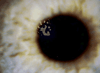

Results: Primary interface complications include infectious keratitis, diffuse lamellar keratitis, central toxic keratopathy, pressure-induced stromal keratopathy (PISK), and epithelial ingrowth. Infectious keratitis is most commonly caused by Methicillin-resistant Staphylococcus aureus (early onset) or atypical Mycobacterium (late onset) postoperatively, and immediate treatment includes flap lift and irrigation, cultures, and initiation of broad-spectrum topical antibiotics, with possible flap amputation for recalcitrant cases. Diffuse lamellar keratitis is a white blood cell infiltrate that appears within the first 5 days postoperatively and is acutely responsive to aggressive topical and oral steroid use in the early stages, but may require flap lift and irrigation to prevent flap necrosis if inflammation worsens. In contrast, PISK is caused by acute steroid response and resolves only with cessation of steroid use and intraocular pressure lowering. Without appropriate therapy PISK can result in severe optic nerve damage. Central toxic keratopathy mimics stage 4 diffuse lamellar keratitis, but occurs early in the postoperative period and is noninflammatory. Observation is the only effective treatment, and flap lift is usually not warranted. Epithelial ingrowth is easily distinguishable from other interface complications and may be self-limited or require flap lift to treat irregular astigmatism and prevent flap melt.